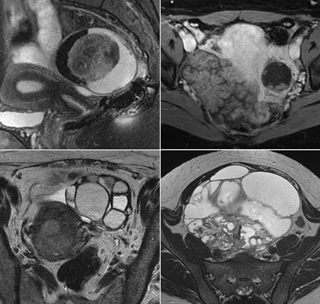

MRI can provide additional soft tissue detail and characterization of ovarian/adnexal lesions and is used as a secondary modality in the O-RADS risk stratification system. The O-RADS MRI lexicon and risk score incorporate terms supported in the literature to describe ovarian/adnexal lesions and assign a risk of malignancy. MRI increases the specificity for the diagnosis of malignancy, due to its ability to detect enhancing solid tissue and can exclude malignancy when there is no enhancing solid tissue.